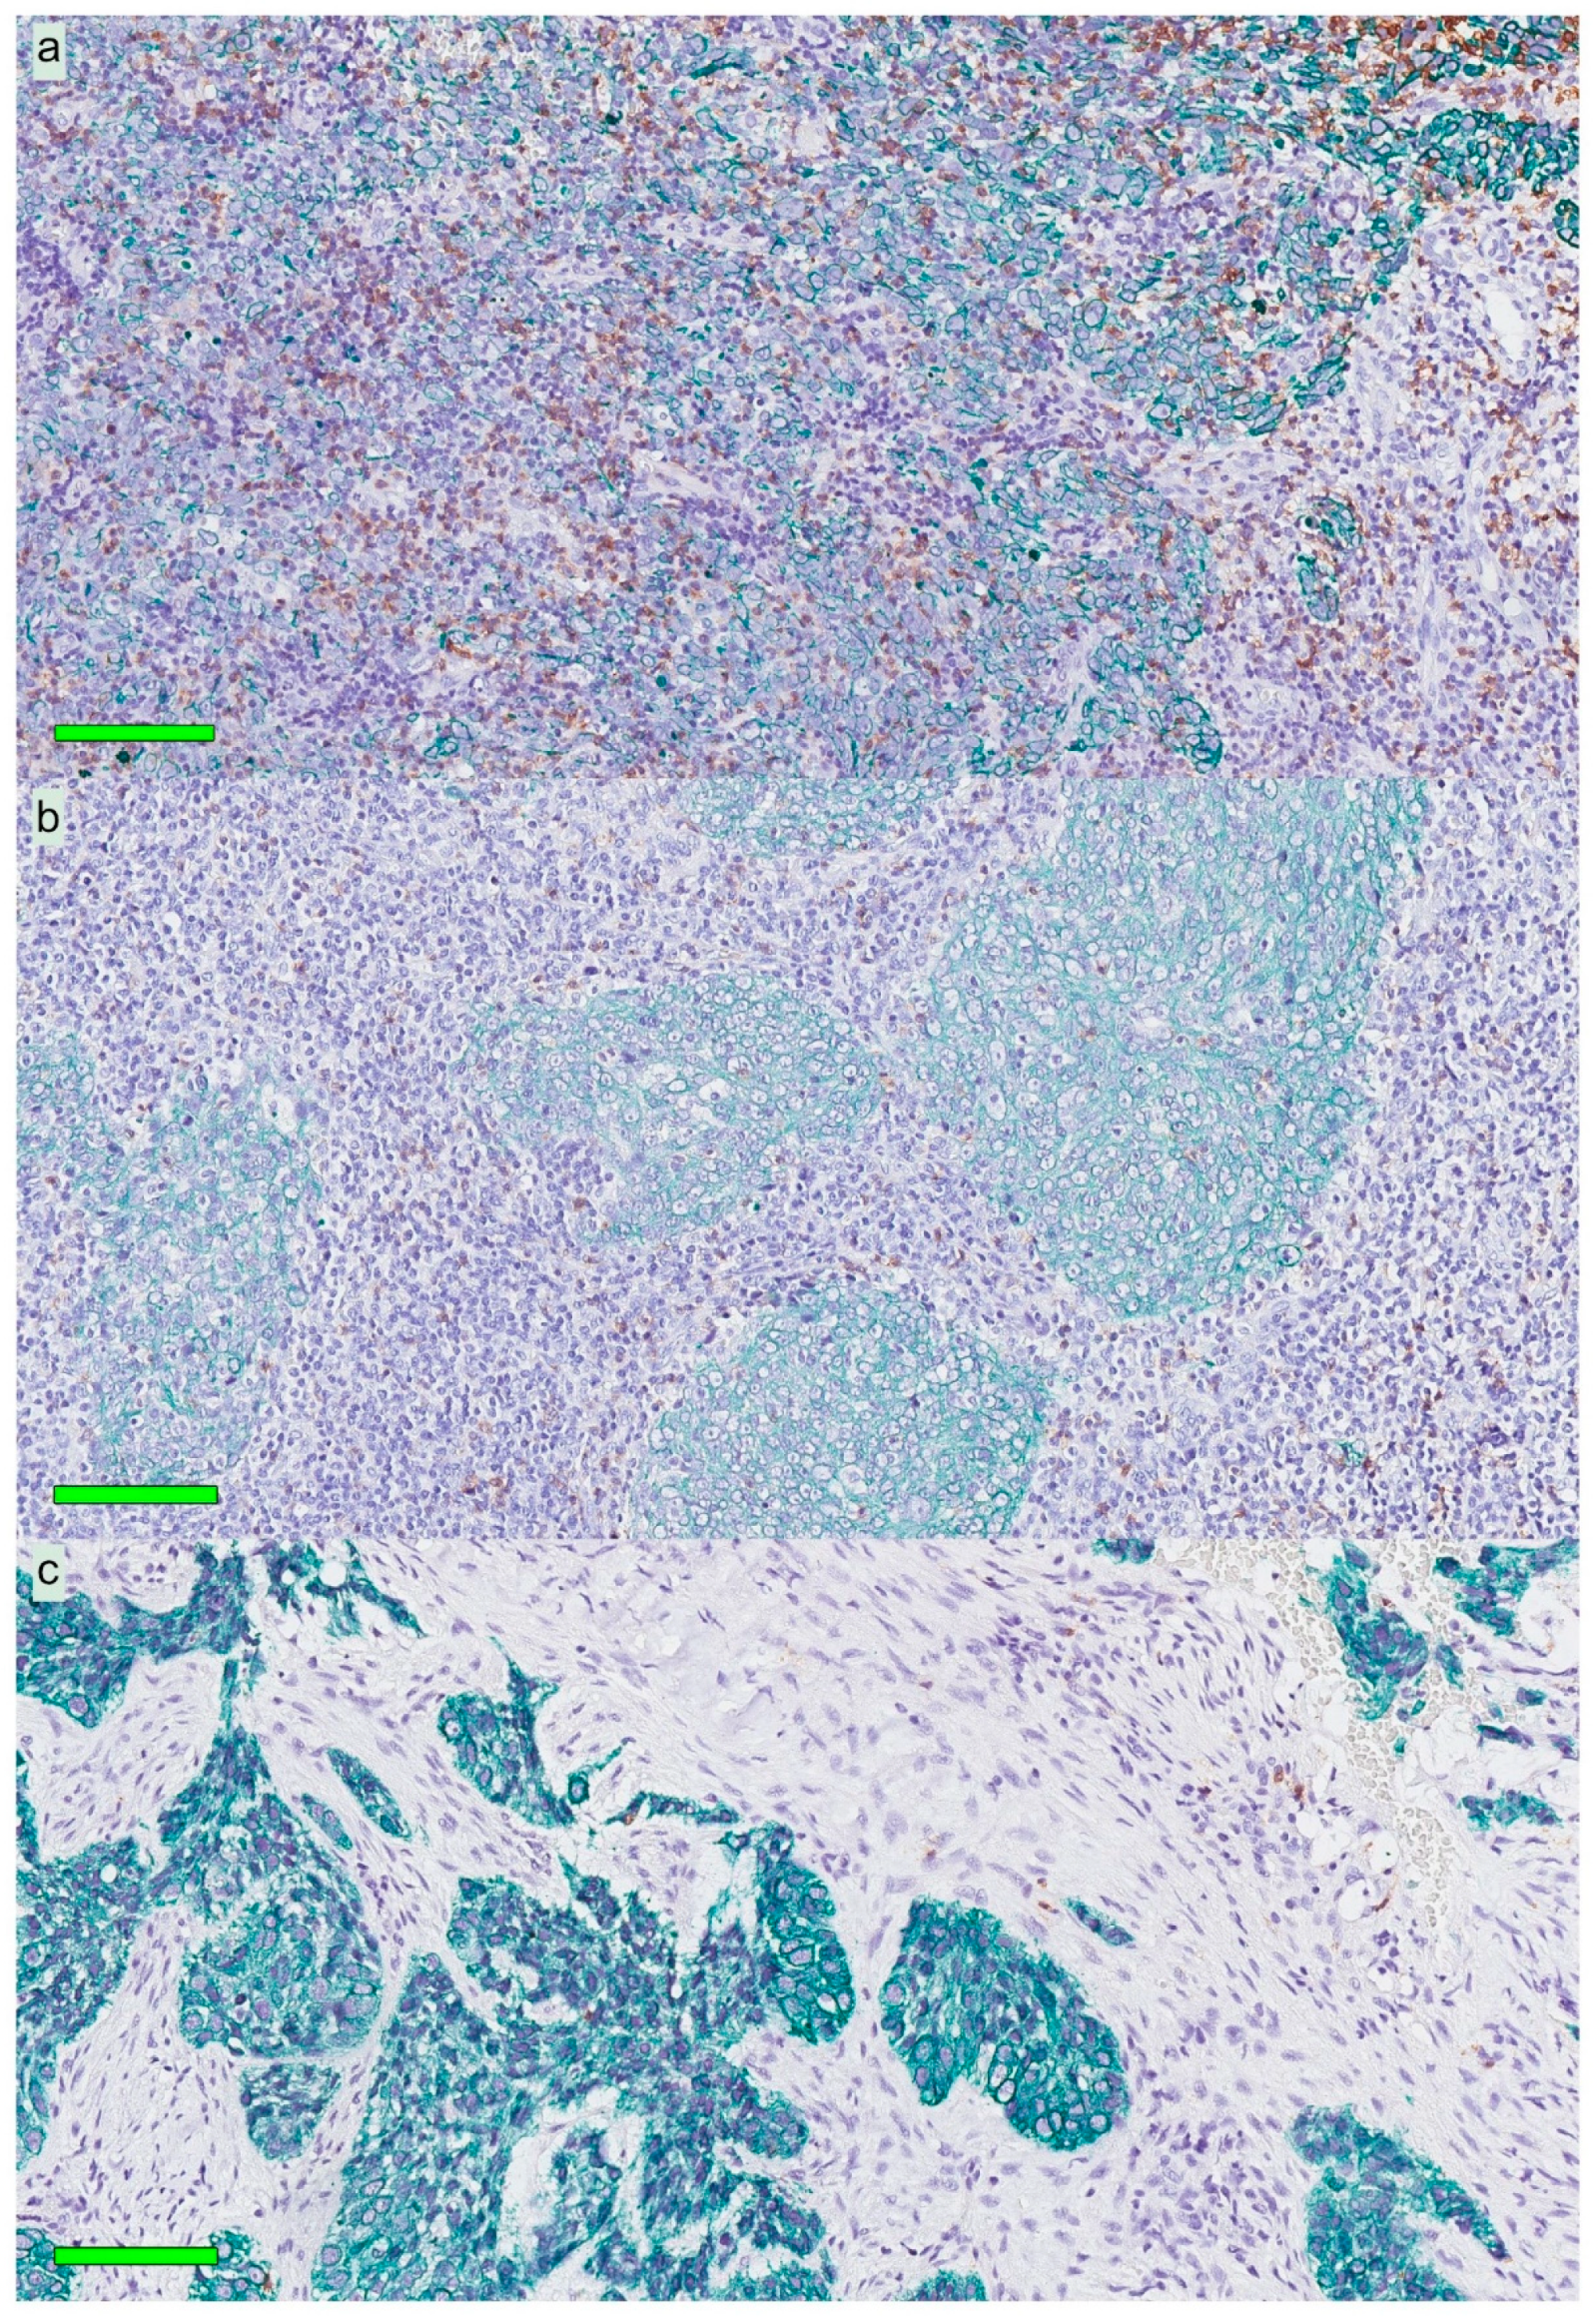

Immune phenotypes of the NPC lesions were estimated based on qualitative assessment of the presence and distribution of lymphocytes on slides stained for hematoxylin, cytokeratin, and CD8. Most lesions (61.7%) were of an immune “inflamed” phenotype (lymphocytes infiltrating cancer cell areas). Immune “excluded” (lymphocytes in the surrounding stroma but not infiltrating cancer cell areas) and “deserted” phenotypes (no lymphocytes in either cancer cell areas or the surrounding stroma) were less frequent: 29.8% and 8.5%, respectively. In Figure 2, selected NPC lesions are presented, demonstrating these three immune phenotypes.

Figure 2. Immune phenotypes for three patients with NPC: Mayer’s hematoxylin in combination with CK (green) and CD8 (brown). All CK expressions denote cancer cells. The top panel (a) shows an “inflamed” tumor rich in infiltrating lymphocytes. The middle panel (b) indicates an “excluded” tumor with lymphocytes surrounding areas of cancer cells. The bottom panel (c) demonstrates a “deserted” tumor with no or very few lymphocytes in areas of cancer cells and the surrounding stroma. Green horizontal bars indicate 100 µm. Abbreviations: NPC = nasopharyngeal cancer and CK = cytokeratin.